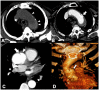

Non-traumatic thoracic aorta emergencies are associated with significant morbidity and mortality. Diseases of the intimomedial layers (aortic dissection and variants) have been grouped under the common term of acute aortic syndrome because they are life-threatening conditions clinically indistinguishable on presentation. Patients with aortic dissection may present with a wide variety of symptoms secondary to the pattern of dissection and end organ malperfusion. Other conditions may be seen in patients with acute symptoms, including ruptured and unstable thoracic aortic aneurysm, iatrogenic or infective pseudoaneurysms, aortic fistula, acute aortic thrombus/occlusive disease, and vasculitis. Imaging plays a pivotal role in the patient's management and care. In the emergency room, chest X-ray is the initial imaging test offering a screening evaluation for alternative common differential diagnoses and a preliminary assessment of the mediastinal dimensions. State-of-the-art multidetector computed tomography angiography (CTA) provides a widely available, rapid, replicable, noninvasive diagnostic imaging with sensitivity approaching 100%. It is an impressive tool in decision-making process with a deep impact on treatment including endovascular or open surgical or conservative treatment. Radiologists must be familiar with the spectrum of these entities to help triage patients appropriately and efficiently. Understanding the imaging findings and proper measurement techniques allow the radiologist to suggest the most appropriate next management step.